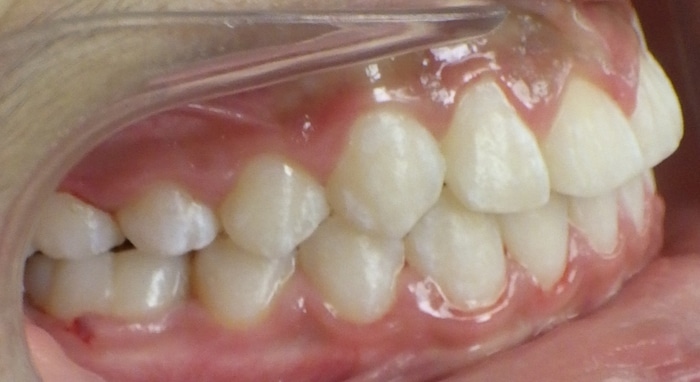

Christopher was a Phase I case that presented with a Class III bite on the right side and around a 90 degree rotation of his upper right central and lateral incisors. During Phase I we placed upper 2×4 brackets (brackets on upper 4 front permanent teeth) since he still had several primary teeth left. We began Phase II and at this time Christopher had 5 mm of upper crowding and 3 mm of lower crowding. We placed brackets on the upper and lower arches and had him wear elastics during treatment. Christopher ended with a really beautiful Class I bite and smile.